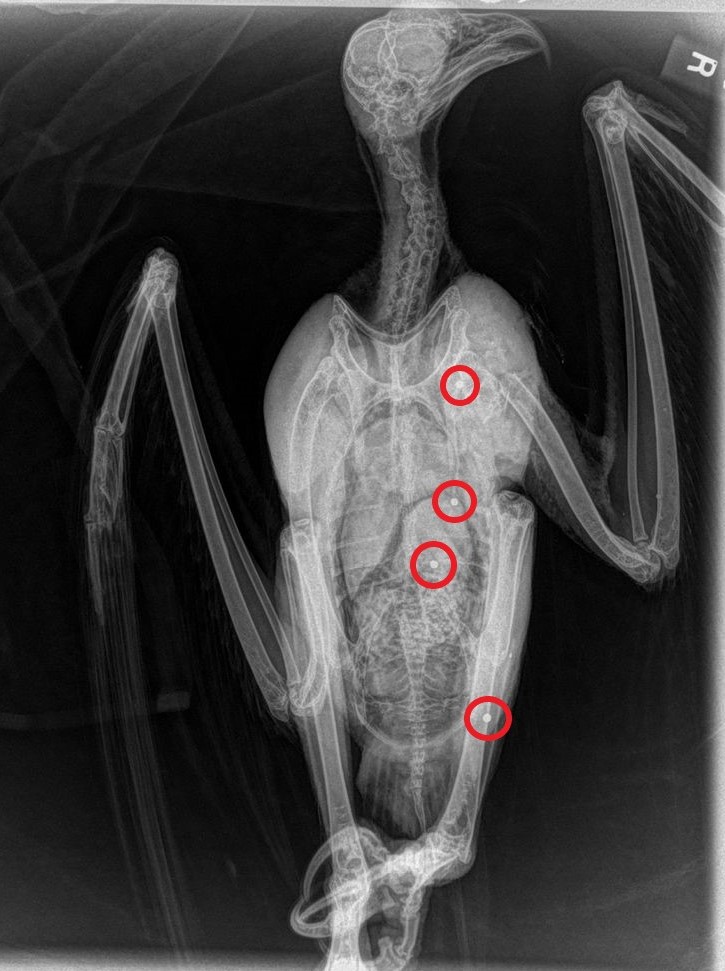

However, the article goes on to claim that the Osprey was ‘shot three times with an airgun‘, but if you look at the x-ray it’s pretty clear that the Osprey has been hit by shotgun pellets (at least four of them – I’ve circled them on the x-ray image below), and not by airgun pellets, which have a distinctively different shape.

The article also claims the Osprey had ‘a ruptured right eye, grazes to its body and a fractured left wing‘. I can’t see the left wing fracture on this particular x-ray but the image of the bird’s left ‘wrist’ area is quite distorted so it’s difficult to tell.

UPDATE 09.30hrs: A vet has been in touch (thank you!) with the following comment: ‘My very rusty veterinary eyes (20 years out of practice!) can see a fracture on the R proximal humerus – also the head of the humerus appears not to be in the shallow socket. Maybe the vet got the L and R markers the wrong way around. Shame there is not a better x-ray after euthanasia. I might be wrong’.

I think I can see a leg fracture also, A short way above the pellet in the same leg; only slightly displaced, so I could be wrong.